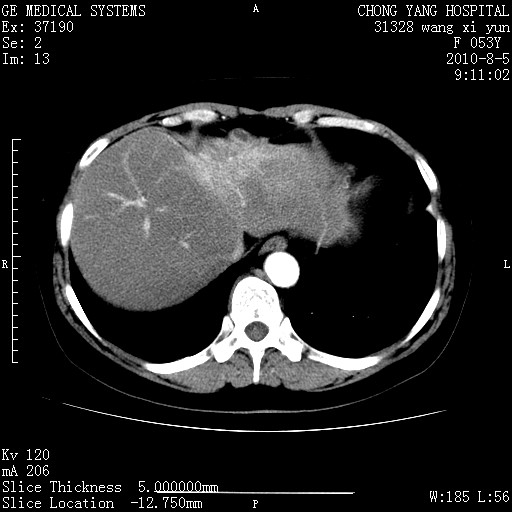

标题: CT28214:F41Y 血尿二十天,建议盆腔平扫加增强。

胆管细胞ca?

1)考虑肝左叶胆管细胞癌。2)脂肪肝。

支持胆管细胞ca。